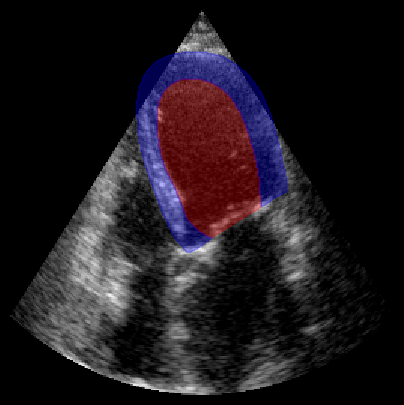

fig, ax = plt.subplots(1, 1, figsize=(5, 5))

ax.imshow(batch_np[0], cmap="gray")

plot_shape_from_mask(ax, masks[0] == 1, color="red", alpha=0.3)  # LV

plot_shape_from_mask(ax, masks[0] == 2, color="blue", alpha=0.3)  # Myocardium

plt.axis("off")

plt.show()